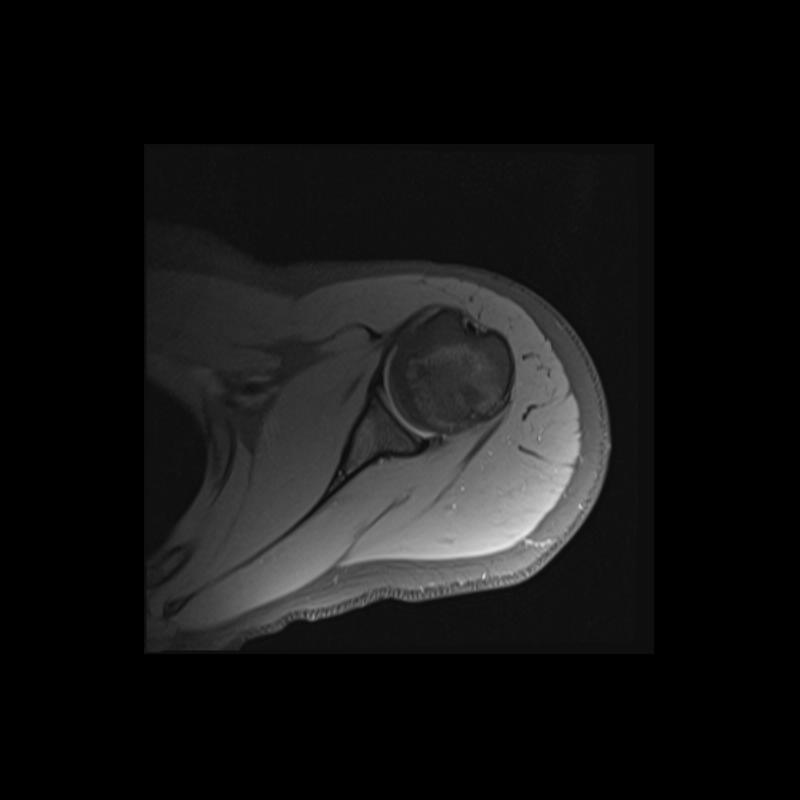

Shoulder MRI Anatomy